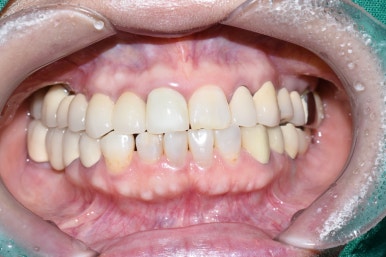

어금니 임플란트 완성 및 임플란트 치료중 사진 (왼) / 완성 후 사진(오른쪽)

어금니 임플란트가 완성된 모습(왼쪽) 및 앞니 임플란트 진행중인 사진과

완성된 사진

기존의 다른 치아와 다른 임플란트, 보철물과 조화를 이루는 앞니 임플란트

완성된 입안에서의 모습 사진입니다.